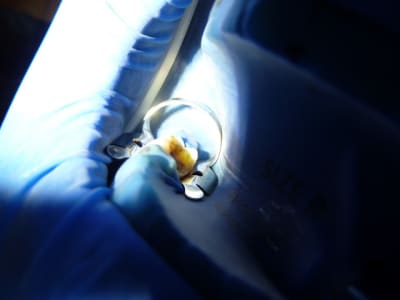

après dépose des amalgames...